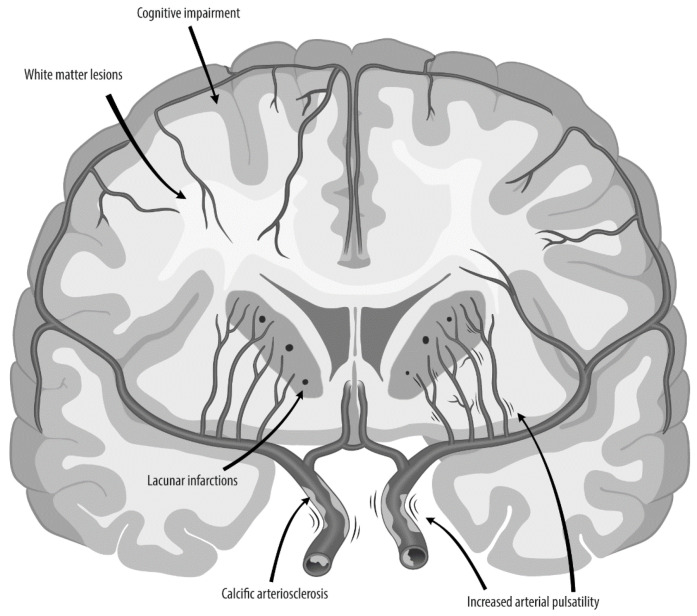

A healthy vasculature with well-regulated perfusion and pulsatility is essential for the brain. One vascular structure that has received little attention is the carotid siphon. The proximal portion of the siphon is stiff due to the narrow location in the skull base, whilst the distal portion is highly flexible. This flexible part in combination with the specific curves lead to lower pulsatility at the cost of energy deposition in the arterial wall. This deposited energy contributes to damage and calcification. Severe siphon calcification stiffens the distal part of the siphon, leading to less damping of the pulsatility. Increased blood flow pulsatility is a possible cause of stroke and cognitive disorders. In this review, based on comprehensive multimodality imaging, we first describe the anatomy and physiology of the carotid siphon. Subsequently, we review the in vivo imaging data, which indeed suggest that the siphon attenuates pulsatility. Finally, the data as available in the literature are shown to provide convincing evidence that severe siphon calcifications and the calcification pattern are linked to incident stroke and dementia. Interventional studies are required to test whether this association is causal and how an assessment of pulsatility and the siphon calcification pattern can improve personalized medicine, working to prevent and treat brain disease.